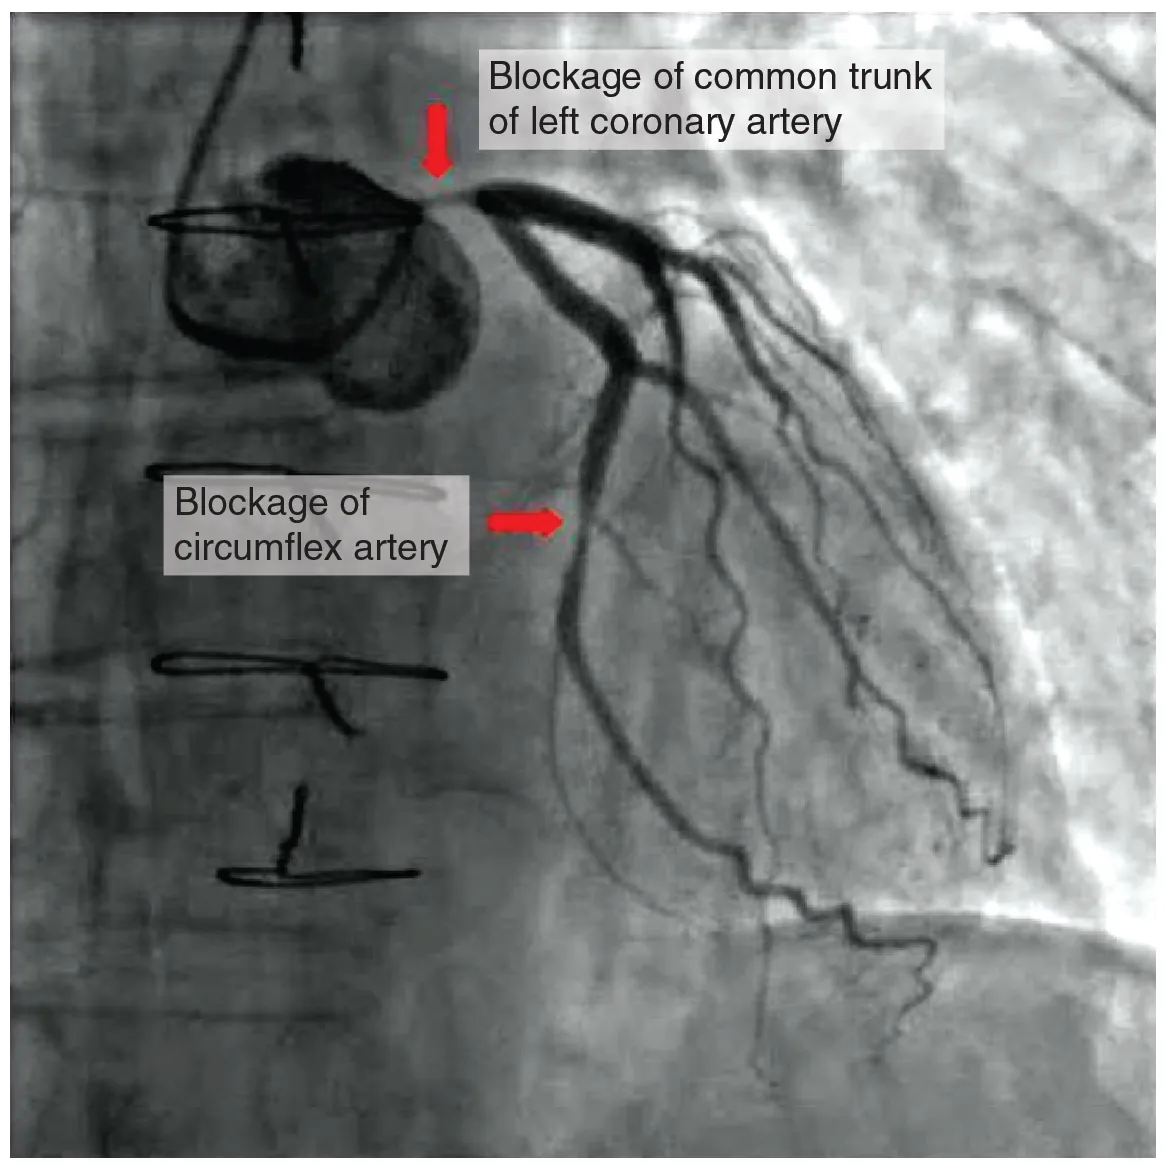

Coronary artery disease is the leading cause of death worldwide. It occurs when the buildup of plaque—a fatty material including cholesterol, connective tissue, white blood cells, and some smooth muscle cells—within the walls of the arteries obstructs the flow of blood and decreases the flexibility or compliance of the vessels. This condition is called atherosclerosis, a hardening of the arteries that involves the accumulation of plaque. As the coronary blood vessels become occluded, the flow of blood to the tissues will be restricted, a condition called ischemia that causes the cells to receive insufficient amounts of oxygen, called hypoxia. Figure 19.16 shows the blockage of coronary arteries highlighted by the injection of dye. Some individuals with coronary artery disease report pain radiating from the chest called angina pectoris, but others remain asymptomatic. If untreated, coronary artery disease can lead to MI or a heart attack.

This photo shows a blockage in the coronary artery and in the circumflex artery.

Figure 19.16 Atherosclerotic Coronary Arteries In this coronary angiogram (X-ray), the dye makes visible two occluded coronary arteries. Such blockages can lead to decreased blood flow (ischemia) and insufficient oxygen (hypoxia) delivered to the cardiac tissues. If uncorrected, this can lead to cardiac muscle death (myocardial infarction).